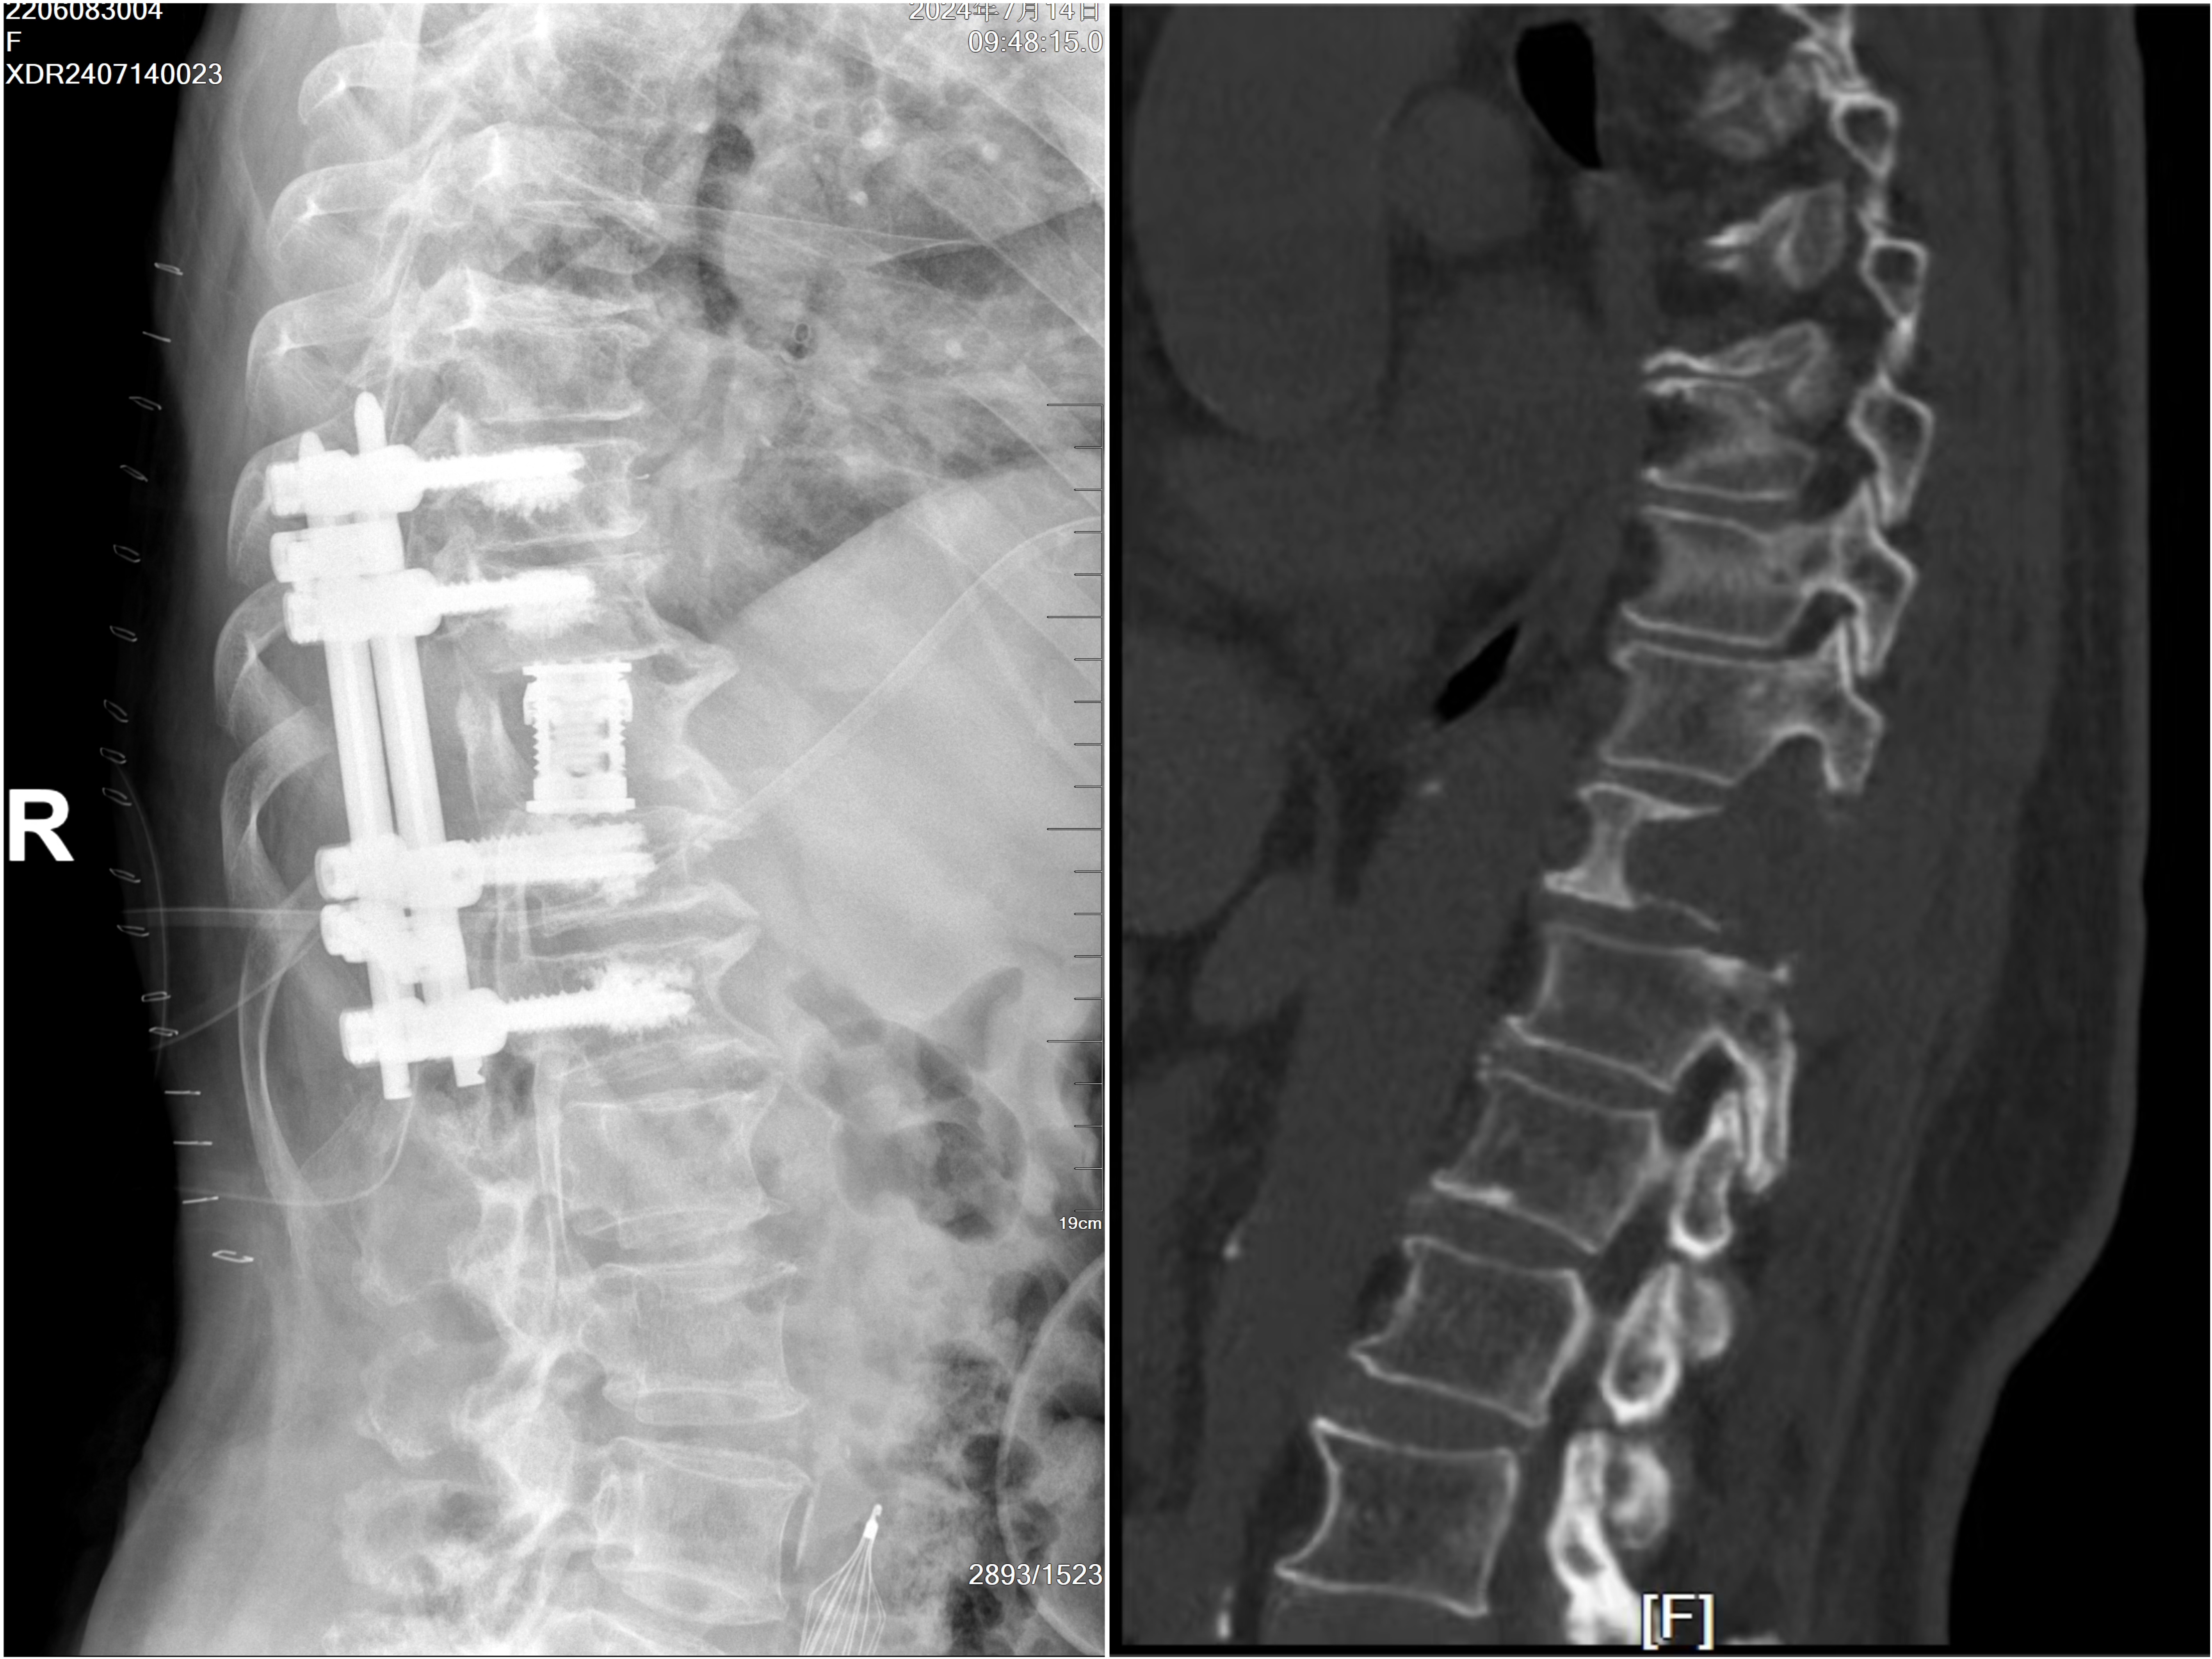

近日,我院脊柱外科在介入科与麻醉科的紧密协作下,成功完成一例高难度椎体肿瘤切除手术。手术的成功标志着通辽市在脊柱外科领域迈出了重要一步,也填补了我地区内此类复杂手术的空白。

该患因受椎体肿瘤折磨2周内病情发展迅速,短时间内下肢功能出现障碍被迫卧床,生活质量急剧下降。面对这一挑战,我院脊柱外科负责人房芳、主任医师吴斌,麻醉科医师宝木兰、介入科医师梁羽,经过术前反复讨论,制定了周密的手术方案和不良事件处理预案,在我院西院区实施手术。手术过程中,脊柱外科专家团队凭借丰富的临床经验与熟练的手术技巧,将肿瘤从复杂的脊柱结构中剥离,同时最大限度地保护了周围的神经与血管,避免了进一步的损伤。介入科利用介入技术,配合手术进行了瘤体滋养血管栓塞,麻醉科团队精准控制麻醉深度,确保手术全程患者生命体征保持平稳。经几组团队通力配合手术圆满完成。术后患者恢复良好,原本瘫痪的下肢开始恢复了肌力。